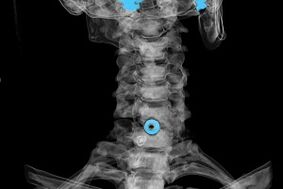

Diagnosis is made based on characteristic symptoms and based on:

- X-rays.The method is ineffective, especially in the final stages of the development of osteochondrosis.

- MRI (magnetic resonance imaging) of the cervical spine.A method that allows you to see bone structures, herniated discs, their size and direction of development.

- Computed tomography.A less effective solution than MRI because the presence and size of hernias are difficult to determine.